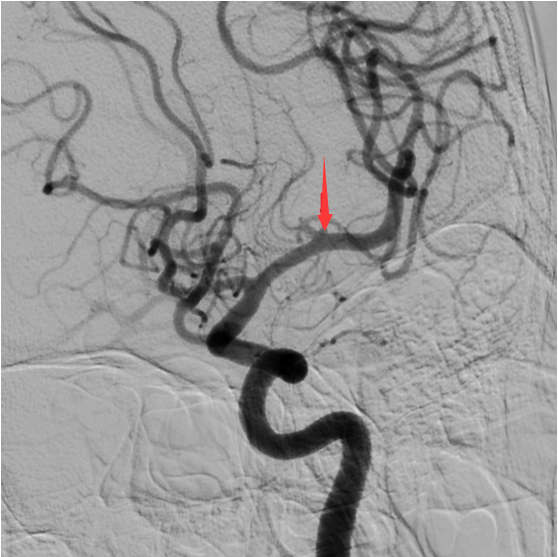

箭头所指为血管同侧的另一个动脉瘤。

可神经外科团队此刻面临的难题是,如果用微创介入疗法处理这种体积微小的复杂动脉瘤,由于操作空间受限,将面临巨大的手术风险。虽然患者年龄大,但考虑到手术安全的可控性,仍建议一侧开颅,行2枚动脉瘤的夹闭手术。

凭借多年丰富的手术经验,神经外科团队很快锁定破裂动脉瘤,术中探查证实与术前分析吻合,为后交通动脉瘤破裂出血造成。经过3、4个小时的紧张手术,将2枚动脉瘤安全夹闭。余奶奶现在恢复良好,已顺利出院。

术后CTA复查影像显示动脉瘤夹闭良好,相关血管保留良好,箭头所指为动脉瘤夹位置。